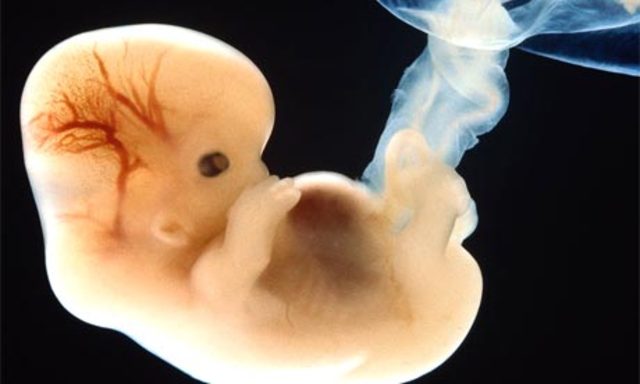

• Week 8

Week 8

The embryo is now around 1.3 cm in length. The rapidly growing spinal cord looks like a tail. The head is disproportionately large

• Week 9.

Week 9.

The eyes, mouth and tongue are forming. The tiny muscles allow the embryo to start moving about. Blood cells are being made by the embryo’s liver.